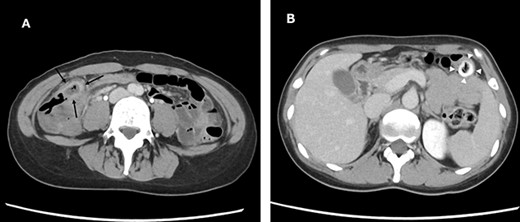

Laparoscopic findings showed that the inflammatory changes were not significant. The surgeon had expertise skills on multiport laparoscopic surgery (MLS) with some SILS experience. Initially, a 40-mm incision was made at the umbilicus. We then performed ileocolic mobilization and lymphadenectomy with ileocolic arterial and venous resection by SILS, similar to MLS (Fig. 3A). Functional end-to-end anastomosis was performed out of the body after removal through an umbilical incision (Fig. 3B and C). The operation time was 2 h and 47 min, and the amount of bleeding was minimal. Macroscopic findings of the surgical specimen showed a diverticulum with an ulcer in the cecal colon, but no fecalith (Fig. 4). Pathological findings showed deep ulceration and abscess formation with no malignant findings. The patient’s course was good, and she was discharged 8 days after the operation.

Intraoperative images. Image (A) demonstrating the anastomotic site (black arrows) and ileocolic artery and veinous dissection (white arrowheads). Image (B) showing the ileocecal region raised outside the body and a diverticulum (white arrowheads). Image (C) shows after closure.